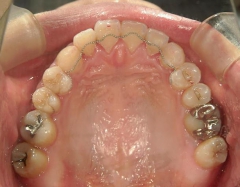

矯正歯科 治療前矯正歯科 治療前

矯正歯科 治療前 急速拡大装置で上顎を広げた後、ワイヤーへ移行 非抜歯

矯正_灰色.pngno.31_7964_治療前_上 .JPG矯正_灰色.png

矯正_灰色.pngno.31_7964_治療前_下.JPG矯正_灰色.png